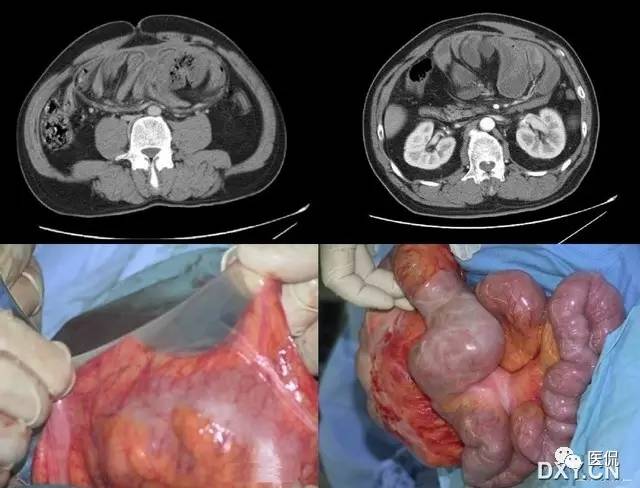

27 腹茧症

全部或部分小肠被一层致密、灰白色的纤维膜所包裹,形似“蚕茧”,故称为腹茧症,又称为特发性硬化性腹膜炎、小肠禁锢症、小肠纤维膜包裹症等。多见于青春期女性。腹部CT十二指肠空肠交界处扭曲,肠系膜增厚伴上消化道扩张,提示不全性肠梗阻。X线可发现全部或部分小肠聚拢于某一部分,位置固定。CT检查有更助于腹茧症的术前诊断。CT能显示梗阻程度及包块内肠管的情况,还能显示包裹在肠管周围的纤维包膜。一旦观察到包膜便可诊断腹茧症。典型的CT表现为扩张的小肠肠袢固定在腹部的某一部位,并被增厚的包膜所包裹或分割。增强扫描示包膜强化明显,部分病例可见腹腔积液及肠管间积液。

鉴别诊断

需要与腹膜包裹症鉴别,后者

(1)结核性腹膜炎所致的腹膜纤维化:表现为腹膜与肠管及网膜间有不易分离的广泛致密粘连,网膜增厚,收缩成团,悬在横结肠处,病理可见典型的干酪样肉芽肿。

(2)腹膜包裹症:表现为小肠包绕在一层相对正常的腹膜当中,与肠管无粘连,肠蠕动不受限,其来源是胚胎发育中残留的脐囊,属发育异常。腹膜包裹症也是一种少见疾病,患者小肠被包绕在一层相对正常的腹膜当中。该病是胚胎发育中脐囊残留,并随小肠发生、发育而被包绕入腹腔,包囊颈部附于十二指肠,又名“十二指肠旁疝”。与腹茧症不同的是,腹膜包裹症小肠外被膜与正常腹膜相似,其内壁与小肠肠管并无粘连,小肠近似位于一个较小的腹膜腔中,肠管蠕动不受限,很少发生肠梗阻。

(3)硬化性腹膜炎:多发生于腹膜透析、腹腔化疗、腹部手术、肝硬化腹水及长期服用普拉洛尔等,全腹紧缩、质硬如板,腹膜壁层及全腹脏器广泛粘连,肠管间粘连紧密,难以分离。